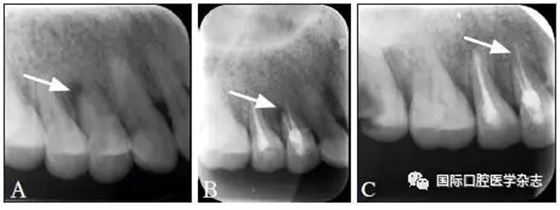

典型病例1 14牙因頸部楔狀缺損穿髓致根尖周炎,根管治療后根尖周透射區(qū)骨質(zhì)修復(fù)(圖1)。

A:初診X線片;B:充填后即刻X線片;C:13個月復(fù)查X線片。

圖 1 14牙根尖周炎經(jīng)根管治療后愈合

Fig 1 The healing of the tooth 14 with periapical periodontitis after endodontic therapy